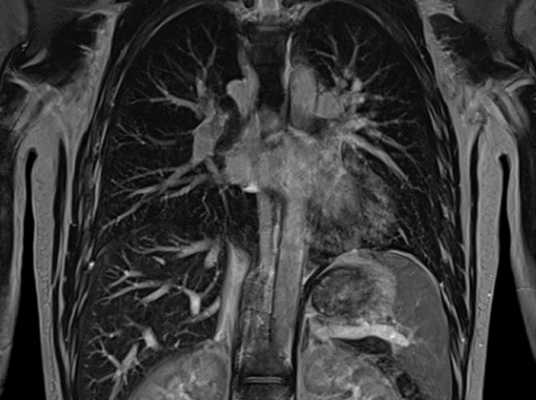

Что показывает МРТ органов грудной клетки

В грудной клетке расположено множество жизненно важных органов, патологии которых сложно диагностировать классическими способами: они скрыты за костями грудины, ребрами, позвоночником, мягкими тканями. Информативным способом, который способен показать структуру, а также функциональность органов, расположенных здесь, врачи называют МРТ — магнитно-резонансную томографию с контрастом или без него. Метод идеально подходит для исследования находящихся внутри грудины органов, сосудов, желез, лимфоузлов, но наиболее эффективным его считают в диагностике опухолевых процессов.

Чтобы понять, что показывает МРТ грудной клетки, важно понимать суть метода. Он состоит в способности мощного магнитного поля провоцировать резонанс молекул водорода, который в больших количествах содержится в органах грудной клетки (сокращенно ОГК). Магнитно-резонансный томограф улавливает резонансные колебания и отображает их на теле-экране в виде серии монохромных снимков, представляющих собой срезы обследуемой области определенной толщины: чем мощнее МР-аппарат, тем «тоньше» срезы и точнее результаты. Также на основе полученных данных можно сделать трехмерную модель любой структуры, находящейся в полости груди.

При использовании контрастного вещества список диагностируемых органов и структур расширяется за счет крупных и мелких кровеносных сосудов. С помощью этого дополнения МР-сканирование показывает не только строение кровеносной сети, но также особенности ее функционирования и изменения в скорости и направлении кровотока. Благодаря тому, что контраст хорошо накапливается в патологических новообразованиях, контрастное МРТ обладает высокой информативностью в диагностике опухолей органов средостения, включая легкие и лимфатическую систему.